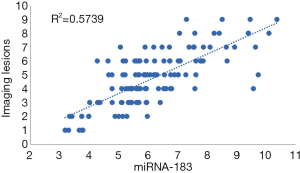

Figure 4 shows the results of Pearson’s correlation analysis. The level of serum miRNA-183 in the CIRI group was positively correlated with the increase of imaging lesions (r=0.758, P<0.0001). R2=0.57 indicates that the regression relationship can explain the 57% variation of the dependent variable.

Increasing attention has been paid to the application of miRNA in clinical practice. The brain tissue is rich in miRNA, with more types and higher expression levels of miRNA than in other organs. The expression of miRNA in the brain is closely regulated, and the expression of miRNA has fixed sequences and regions during the development of the brain (15). When the body is geomagnetic, miR-183 exists in sense organs, and when cancer, neurological disorders, or autoimmune disorders occur, miR-183 has a higher expression in the non-sensory organs. In etiology research and target therapy, the use miR-183 and some associated factors has gradually increased for the diagnosis, prevention and treatment of CIRI (16). miR-183 also exhibits specific expression in the human and mouse cerebral cortex, affecting the development of the cerebral cortex and regulating the differentiation of nerve cells. For example, after dorsal root ganglion injury in adult rats, the expression of miR-183 was significantly decreased, and its distribution was closely related to stress granule (SG) protein, suggesting that the regulation of chronic neuralgia by miR-183 could be realized through pain-related genes (17). Yuan et al. (18) found that miR-183-5p increased in the hippocampus under chronic and persistent mild mental stress, indicating that the increased miR-183-5p level was associated with stress-induced depression. Meanwhile, miR-183 was demonstrated to interfere with glucose and lipid metabolism, and its abnormal expression has been related to metabolic diseases like obesity and diabetes, and it has been shown to induce cerebrovascular diseases, such as atherosclerosis (19). In this study, RT-qPCR detection found that, compared with the control group, the level of miR-183 in peripheral blood of patients with CIRI was significantly higher than that of the control group. Meanwhile, the level of serum miR-183 in the CIRI group was positively correlated with the increase of imaging lesions. These results confirm that miR-183 is involved in the occurrence and development of ischemia-reperfusion. MiR-183 can inhibit the activation of microglia and the expression of inflammatory factors through NF-κ-signaling pathway (20). Down regulation of miR-451 can promote angiogenesis by targeting macrophage migration inhibitory factor in hypoxic human umbilical vein endothelial cells, indicating that miR-451 is a potential candidate for the treatment of cerebral ischemia injury (21). SNHG1 targets miR-199a and up regulates SIRT1 expression, thus alleviating cerebral ischemia/reperfusion injury through AMPK pathway activation (22).